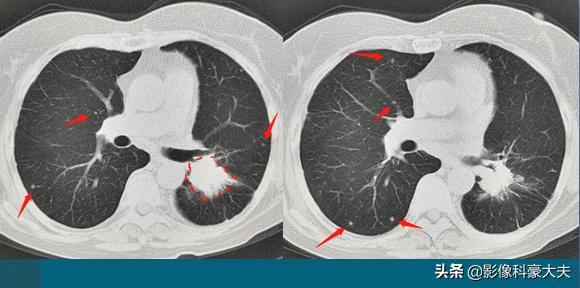

这位病人才61岁,咳嗽1个月,伴有喘息和憋气,肺部CT发现左侧中心型肺癌,3.6×2.6cm,不算大,却已经无法切除了,因为双肺见到十多个像黄豆大小的转移瘤,晚期了……

这位病人的生存期,相对比较乐观!如果基因检测阳性,通过靶向治疗为主的综合治疗,还有机会生存3年以上,甚至10年!

豪大夫不是吹牛,很多晚期肺癌病人都在创造和延续奇迹!今天还有一位复查的病人,3年半前确诊为肺癌晚期,双肺一百多个转移瘤和多发骨转移:

这位病人67岁,男性,因为咳嗽、胸痛做肺部CT,右上肺癌3.1cm,边缘有毛刺。因为肿瘤贴近胸膜,癌细胞沿着胸膜脉管系统(主要是淋巴系统)快速播散,像种子一样在双肺生根发芽,长出100多个转移瘤,还有胸椎、肋骨的多发骨转移,已经无法手术。